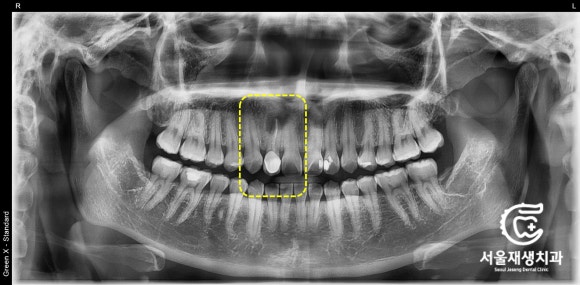

파노라마 엑스레이

![[재신경치료] 소중한 내 앞니...재신경치료로 다시 한 번 살려 쓸 수 있습니다. (서울재생치과, 현미경신경치료) 관련 이미지 3](https://pub-9f2bb3498faf4d1d8714b41df24753e3.r2.dev/content/clinics/archive/nqmm0udu86/naver_blog/honeybeevuvu/assets/by_hash/943b25df7e89de742f550a3af247f75bab9cabe2a4abcd1c63d3b2303e150fa9.jpg)

치과 검진을 위해 가장 기본적으로

촬영하는 사진입니다.

파노라마 엑스레이라고 하는데요,

원인이 되는 치아의 정확한 위치와

대략적인 컨디션을 파악할 수 있는

가성비 최고의 검사입니다.

노란상자로 표시된 부분을 보겠습니다.

앞니의 뿌리 끝에

검은 구멍이 보이네요.

염증 때문에 뼈가 흡수된 것 같습니다.

좀 더 자세히 살펴보겠습니다.